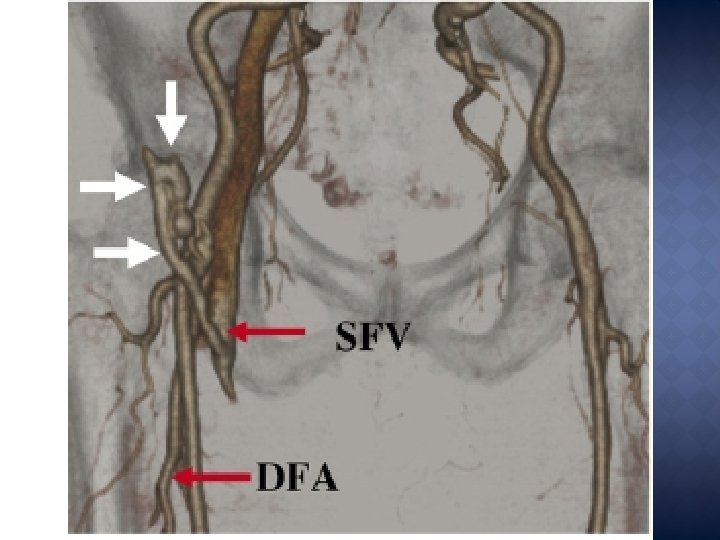

� L’AFC - - (donc infra-inguinale) = site idéal: Diamètre large Situation superficielle horizontale Caractère souvent moins pathologique Compressibilité : contrefort osseux (tête fémorale) Faible compliance du tissu mou autour Taux de complications plus élevé si la ponction est: Haute = supra inguinale (IE) : hématome rétropéritonéal, FA 12, 9% v/s 3, 1% Basse = AFS/AFP: FA 8, 9% , FAV, spasme (diamètre), hématome, occlusion

� Idéalement: 2 -3 cm sous le ligament inguinal (LI) clinique � Travaux de Rupp comparant anatomie/repère clinique/ repère radiologique du LI

� En regard de la portion moyenne de la tête fémorale (1 cm latéralement par rapport à sa corticale médiale) � J. Ng et Yamen : 20 cas: 100% avec RX, 65 % sans � Choong : 279 cas: 85% AFC avec RX, 75% sans. � Limite = variantes anatomiques.

Avec repères radiologiques: 1) Calcifications pariétales de l’AFC 2) Tete femorale portion moyenne Avec Echo-guidage Ponction de l’AFC controlatérale et montée de guide jusqu’à l’AFC voulue , en guise de repère.